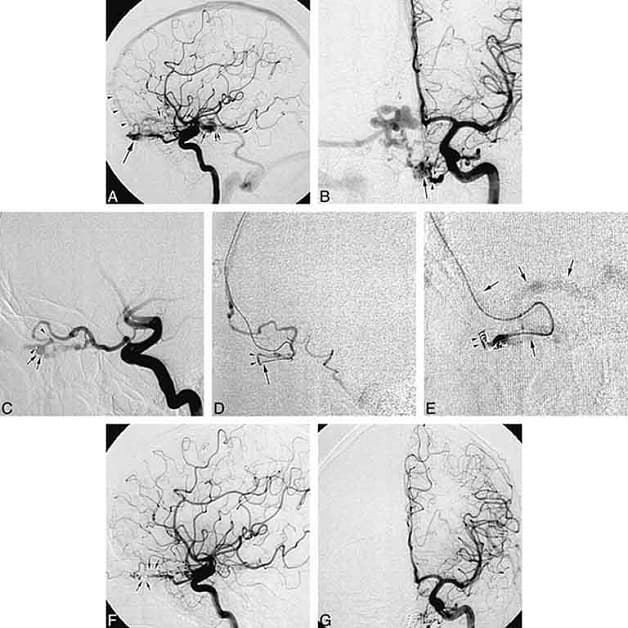

2.5. Chụp mạch số hóa xóa nền DSA

Trong các phương pháp chẩn đoán thiếu máu não, kỹ thuật chụp mạch số hóa xóa nền DSA cũng là một trong những phương pháp thường được sử dụng. Đây là kỹ thuật sử dụng hệ thống tia X để chụp hình mạch máu với mục đích nghiên cứu các mạch máu để xác định các vị trí tổn thương và bệnh lý mạch máu trước khi tiến hành điều trị.

Chụp mạch số hóa xóa nền DSA đang là phương pháp có nhiều ưu điểm nhất và được sử dụng rộng rãi trong quá trình chẩn đoán bệnh thiếu máu não hiện nay.

Đây là một phương pháp được ứng dụng để phát hiện rất nhiều căn bệnh như:

– Phát hiện sớm một số bất thường của các mạch máu não, thăm dò và chữa trị điện sinh lý, u não, ung thư gan,…

– Dễ dàng đánh giá được những dị thường của động mạch thận, động mạch chi, động mạch chủ, các động mạch ngoại biên,…

Kỹ thuật này giúp sớm phát hiện những vấn đề bất thường của dòng máu gây ảnh hưởng tới các tế bào não. Từ đó, các bác sĩ sẽ đưa ra hướng điều trị phù hợp cho bệnh nhân. Tuy nhiên để đảm bảo an toàn, người bệnh cần tuân thủ chặt chẽ các chỉ định của bác sĩ trong quá trình thực hiện.